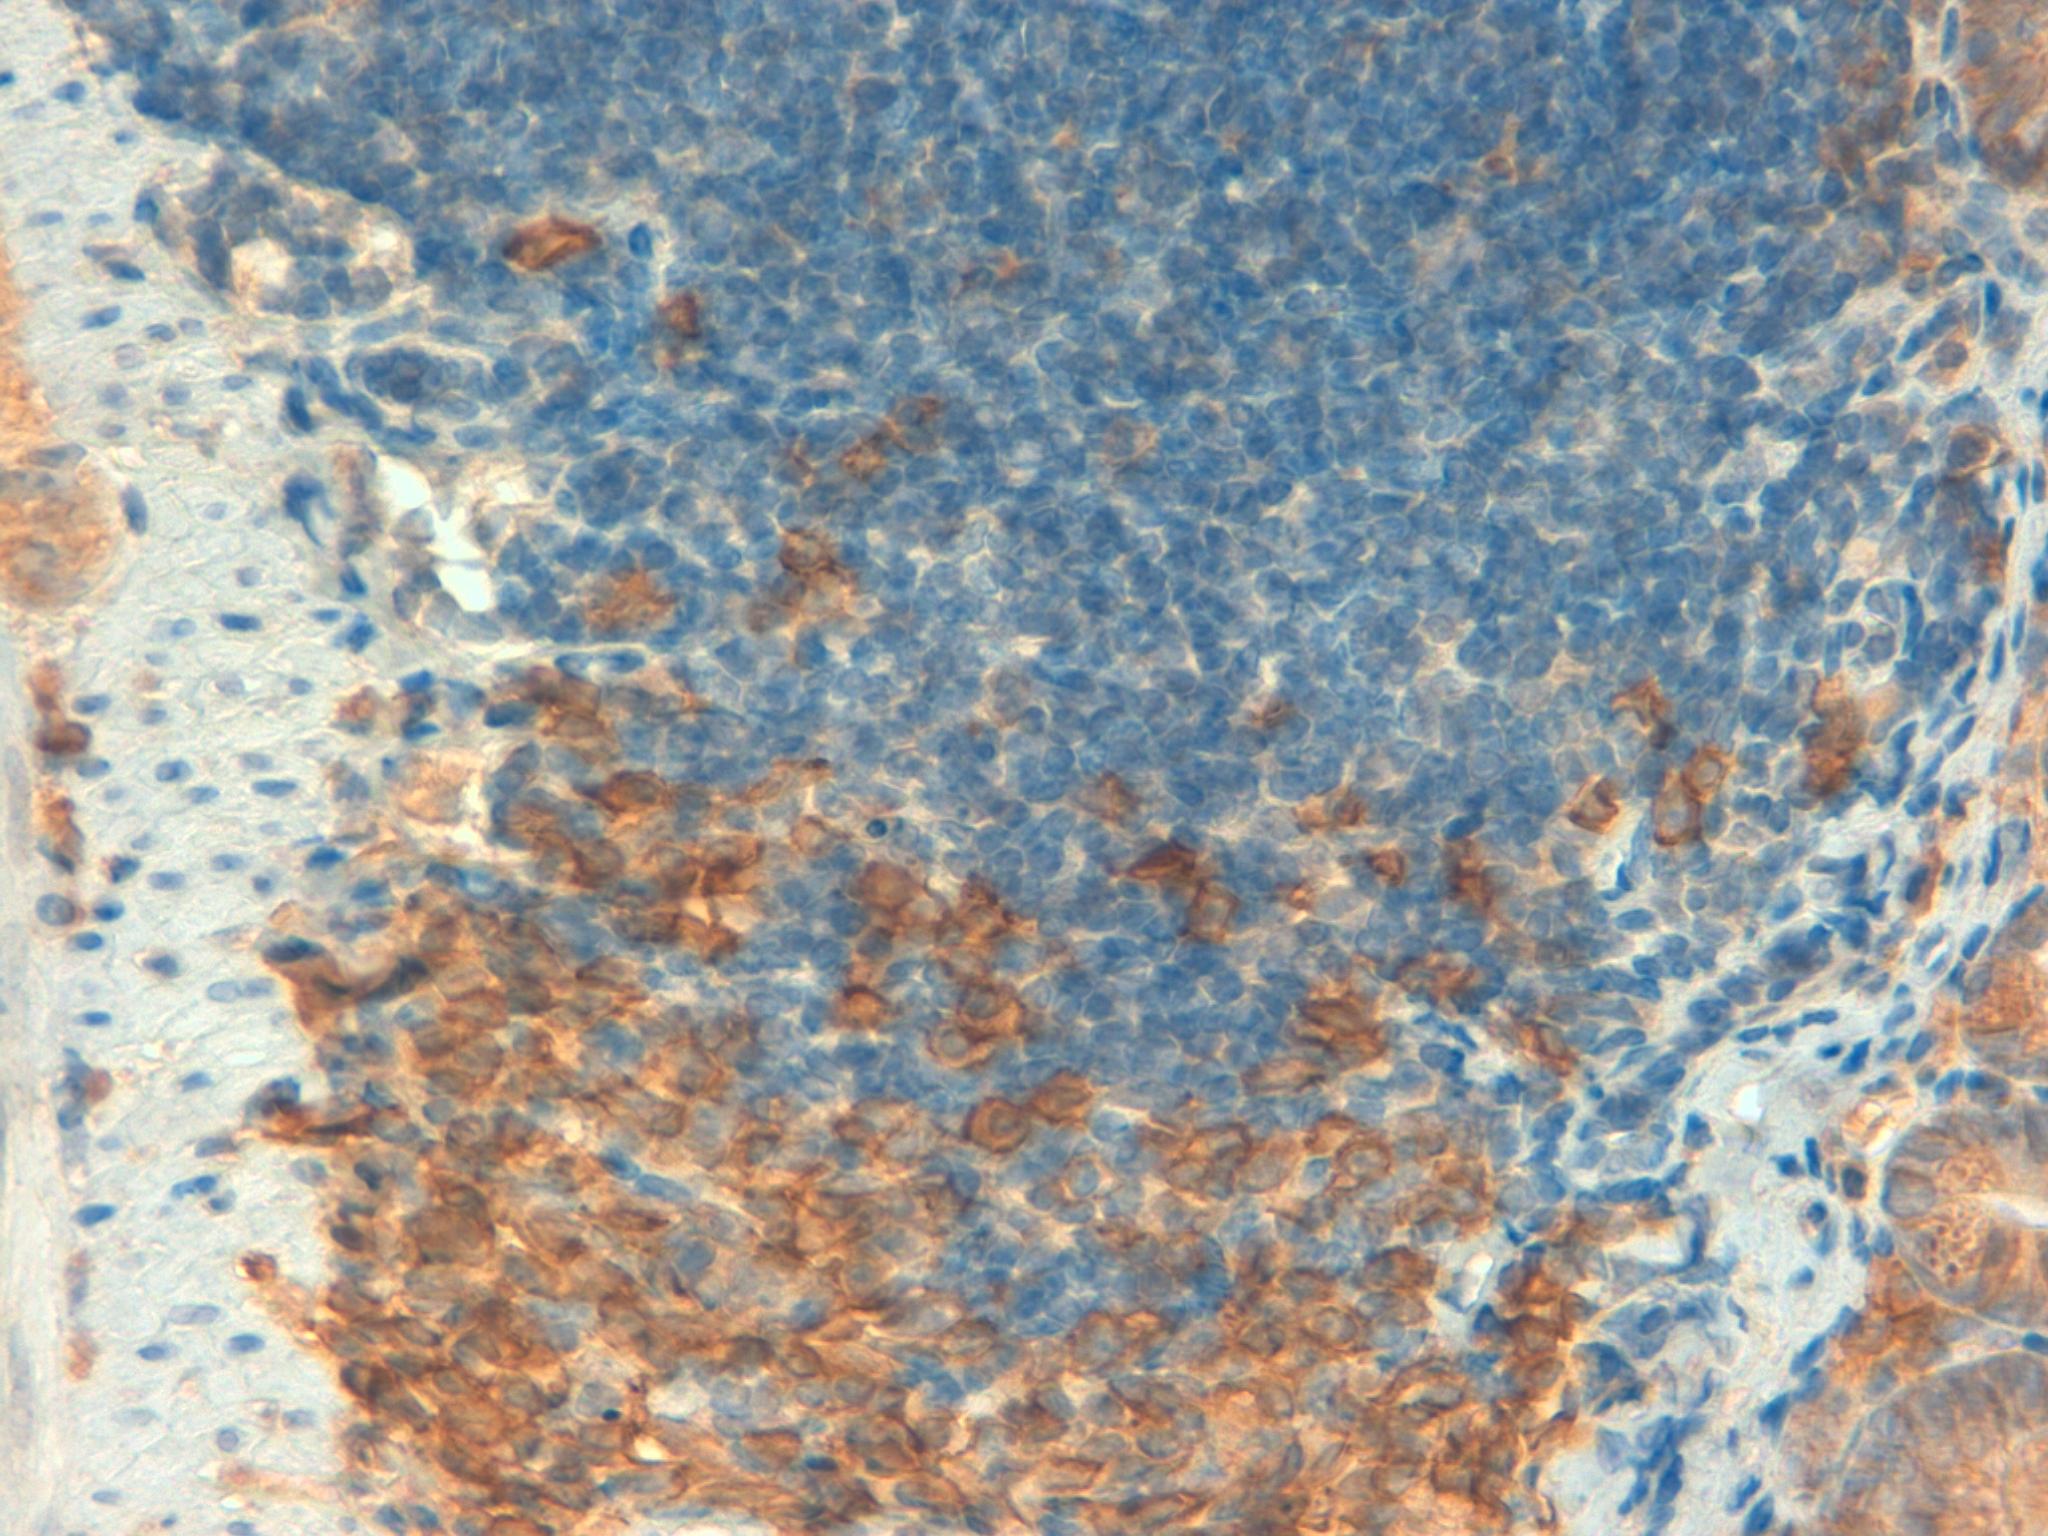

Mouse colon 40x lamda chains

Mouse colon 40x CD138

Mouse colon 40x F4 80

Mouse colon 40x kappa chains 2

Mouse Colon 40x CD3

Mouse Colon 40x GRI

Mouse Colon 40x CD45